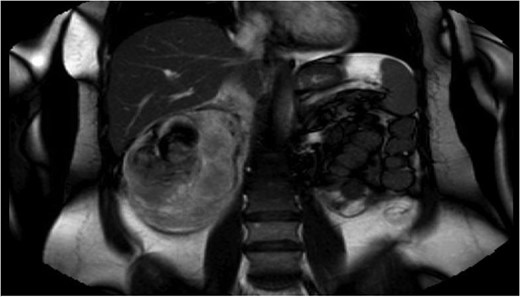

Fluid resuscitation and IV antibiotics were commenced, and an abdominal ultrasound performed. It revealed the presence of a large heterogenous right renal mass. Further evaluation was performed with magnetic resonance cholangiopancreatography. Findings were of a 5.7 × 4.6 cm2 exophytic mass of high T1 signal intensity arising from the posterior right kidney. Adjacent to the mass was a large 8.3 × 10 cm2 retroperitoneal haematoma (Fig. 1). These findings were consistent with a ruptured angiomyolipoma. The adjacent common bile duct was dilated at 8 mm, secondary to mass effect (Fig. 2).

Admission imaging revealing dilatation of the common bile duct (8 mm), due to external compression.